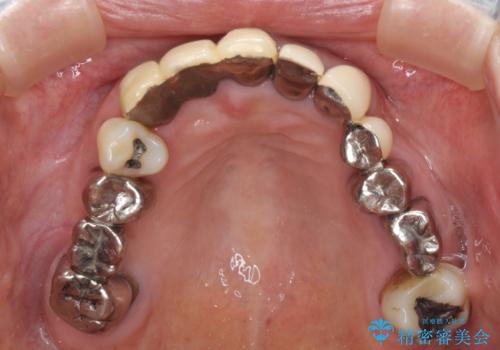

着色が著しい前歯のブリッジをオールセラミックできれいに

- 保険診療の前歯のブリッジが、形態も色も不自然で気になるとのことで来院された患者様です。

神経の抜かれている土台の歯は根管治療を行った上で、オールセラミックブリッジにより補綴することとしました。